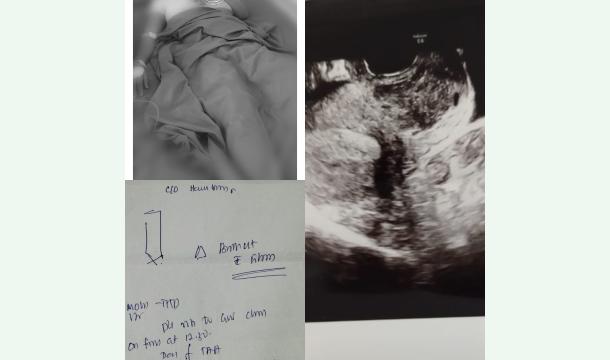

• recently I went through a very painful time in my life. Due to fibroids, I had to undergo surgery and lost my womb. It was not only physically painful but emotionally heartbreaking.Now,

I am seeking support to raise CHF 1,500 to help me settle this amount. Any contribution, big or small, would mean so much to me.